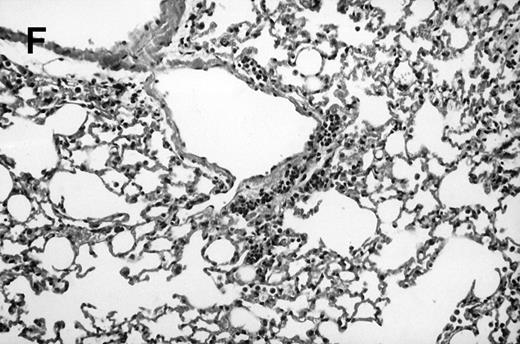

Allogeneic transplanted mice (B10.BR → CBA) with GVHD and, as controls, allogeneic transplanted mice without GVHD and syngeneic transplanted mice (B10.BR → B10.BR) were infected intranasally with HSV-1 at 12 weeks after transplantation. As an additional control, age-matched normal CBA mice were infected as well. Histological examination of lungs was performed in mock-infected mice and in mice at day 7 after infection. Allogeneic transplant recipients with GVHD showed increased pathology (Fig 1). Scores reflecting the periluminal histopathologic changes were significantly higher (P = .05; Student's t-test) in allogeneic transplant recipients with GVHD, when compared with control mice (Fig 2). The periluminal histopathologic scores were also higher in allogeneic transplant recipients with GVHD, when compared with normal CBA mice, at days 4, 10, and 14 after infection (data not shown). No significant differences were observed in the scores reflecting the parenchymal histopathologic changes (data not shown). Because the results in syngeneic transplanted mice were very similar to those in allogeneic transplanted mice without GVHD, the latter, which are the most appropriate control for procedural effects and for the effect of GVHD, and normal CBA mice, were used as controls in further experiments.

Allogeneic transplant recipients with GVHD showed increased pathology. Photomicrographs of lung sections stained with hematoxylin and eosin show evidence of increased pathology in infected allogeneic GVHD mice. (A) Normal CBA, mock-infected, original magnification × 25; (B) normal CBA, mock-infected, original magnification × 100; (C) normal CBA, infected, original magnification × 40; (D) normal CBA, infected, original magnification × 100; (E) allogeneic GVHD, mock-infected, original magnification × 10; (F) allogeneic GVHD, mock-infected, original magnification × 75; (G) allogeneic GVHD, infected, original magnification × 10; (H) allogeneic GVHD, infected, original magnification × 100.